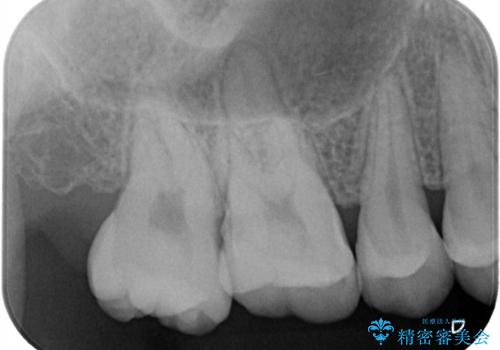

【セラミックインレー】咬合面のカリエス

- メンテナンス時に見つかった虫歯です。二次カリエスのリスクを下げる為に虫歯を除去後セラミックインレーで治療を行いました。

咬合面の溝が深く虫歯のリスクが大きい患者様です。

他の歯も咬合面に同じように虫歯ができて大きくなってしまった経験があることから今回は大きくそして深く進行する前に虫歯を除去しセラミックインレーで治療を行いました。